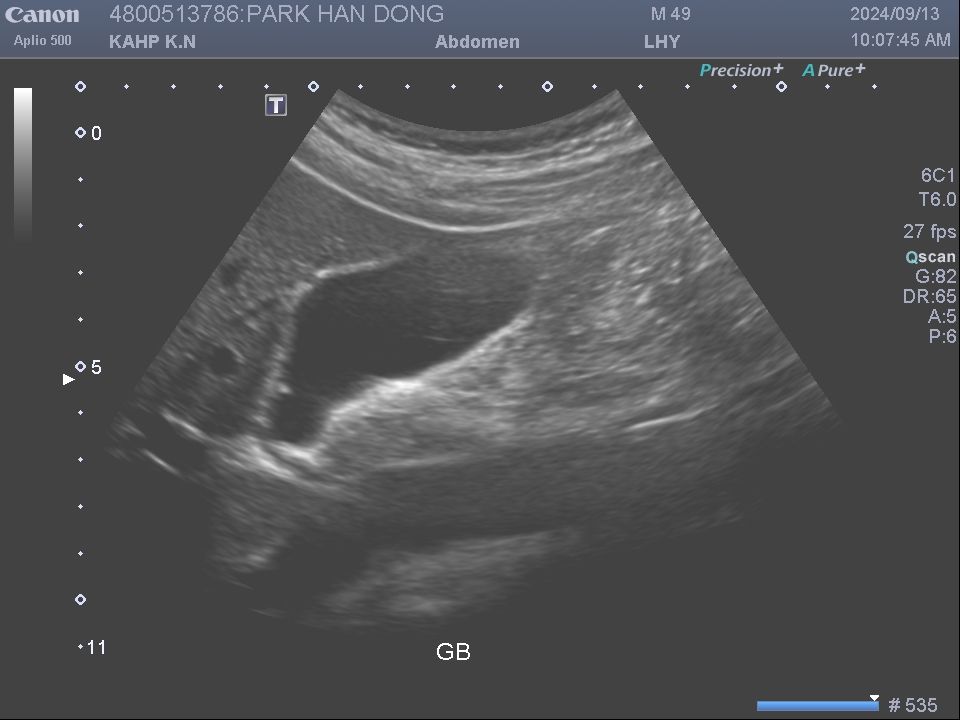

우측복부 통증원인, 담낭, 신장, 충수염 무슨문제 일까요?

새벽에 우측 복부 불편감에 잠을 깹니다. 통증이 심한건 아닌데... 가스가 차서 그런건지... 그리고 낮에는 우측 상복부 갈비뼈 근처에 불편감이 있습니다. 가끔씩 옆구리에 오기도 합니다. 이러한 증상이 올해 초부터 있다 없다를 반복합니다. 동내 내과 병원에서는 딱히 진단이 없습니다. 소화불량 정도... 초음파나, 피검사에서도 크게 특이점은 없었습니다. 그런데 최근 건감검진을 하고 담낭에 용종 3.1mm 와 우측 신장에 물혹 10mm가 추가 발생하였습니다. 원래 우측 신장에 13mm 물혹이 하나 있었는데 추가적으로 하나가 더 생겼습니다. 3개월전 동내 초음파에서 없던 증상들이 갑자기 나타 날수 있나요? 그리고 이러한 증상때문에 우측 복부에 불편감이 오는걸까요?

그리고 혹시 담낭용종은 사진상 암은 아닐까요? 몸에 나타나는 상복부, 옆구리 통증이 혹시 충수염 가능성이 있나요? 비슷한 증상의 지인이 얼마전 충수염 수술을 했다고... ㅜ ㅜ 이래 저래 여러가지 생각이 듭니다... 어떻게 해야 할까요...ㅜㅜ

• 1번 째 사진

2. 담낭 용종이나 신장 물혹 모두 이야기 하신 것 같은 증상을 유발할 가능성이 있습니다.